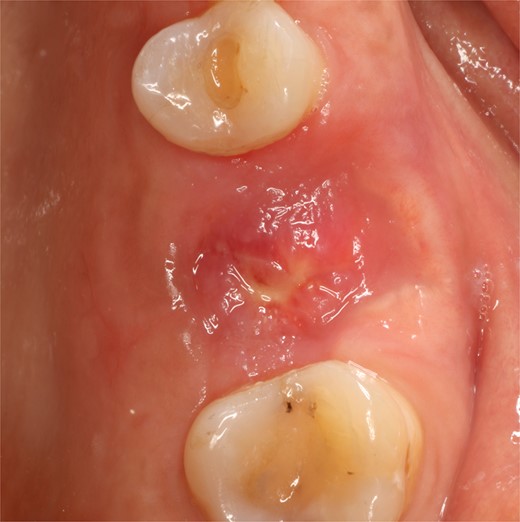

Following local anesthesia, an intrasulcural incision was made from the distal surface of the premolar, continuing through the sulcus to the mesial surface of the second molar in the vestibular and palatal surfaces. After the molar was extracted, granulation tissue was observed inside the socket that continued inside the maxillary sinus (Fig. 3); The socket was scaled, washed, and rinsed with physiological saline. The labial and palatal mucoperiosteal flaps are raised with full-thickness tunneling of the tissue, exposing the labial and palatal bone plates to allow a space for the ribose-crosslinked collagen membrane that will be used for socket closure. A 5 mm × 10 mm × 10 mm collagen sponge with hydroxyapatite and ribose was used, which was taken to the alveolus without hydration so that it absorbs as much blood as possible. It is important that the sponge has retention in the alveolus so that it does not displace within the maxillary sinus and is positioned at the same level as the remaining bone crest. A collagen membrane crosslinked with ribose was placed from buccal to palatal under the tunneled tissues (Fig. 4). A 5–0 absorbable monofilament suture was used, another layer of the collagen membrane was used in the occlusal area that was exposed, and two horizontal mattresses were sutured to give stability to the biomaterials (Fig. 5).

A control appointment was made 8 days later, and the scar tissue with slight erythema on the edges of the alveolus was observed (Fig. 6). The patient was asymptomatic, and the membrane was in position to cover the entire alveolus. After the fourth week, granulation tissue was observed covering almost the entire alveolus, and an area was observed where the membrane found below this granulation tissue could be seen (Fig. 7). About 3 months after surgery, healed soft tissue was observed, and a CT scan was requested, where the maxillary sinus was observed without evidence of pathologies and hypodense alveolar bone compatible with immature bone in the process of calcification (Fig. 8). After 6 months, keratinized tissue and a completely healed alveolus were observed (Fig. 9), and cone beam computed tomography (CBCT) was requested to evaluate the results and see the possibility of placing an implant. In the CT scan, continuous sinus and alveolar cortex were observed with an image compatible with bone in the healing process (Fig. 10).